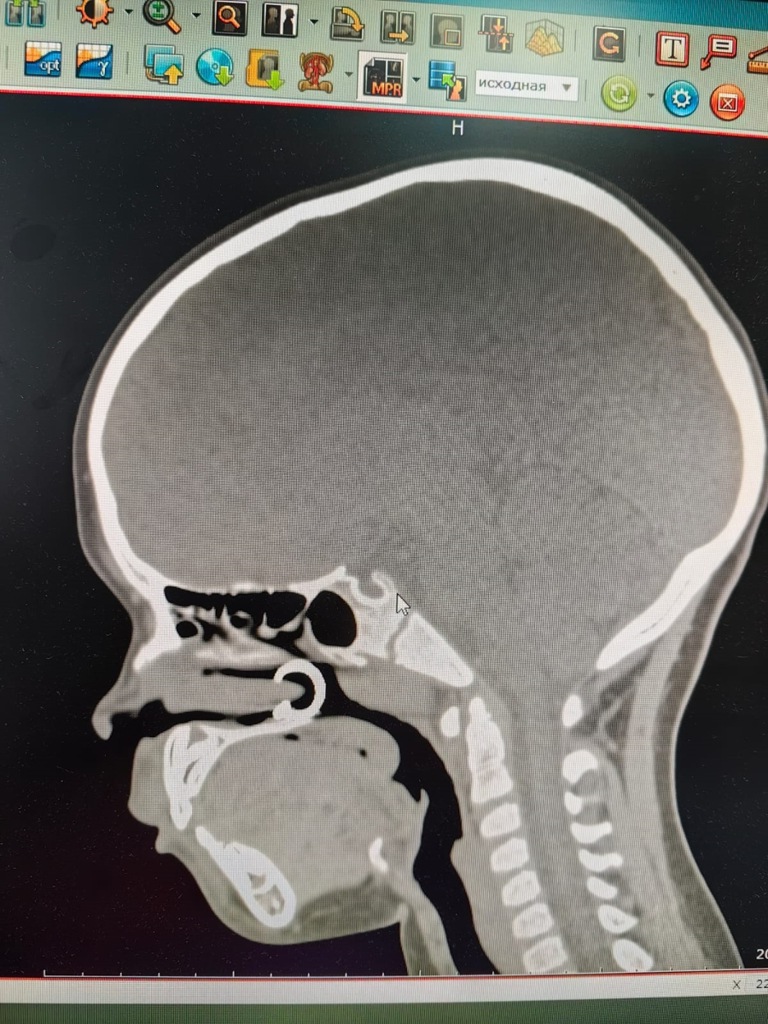

"К нам обратилась маленькая пациентка, которая вдохнула через нос сережку-пирсинг. Со слов родителей девочка решила повторить за своей старшей сестрой и надеть сережку на нос. После проведенного рентгенологического исследования была проведена эндоскопическая операция по удалению инородного тела. Все прошло успешно, и девочку отпустили домой", - рассказала врач-оториноларинголог Алена Фуфаева.

Специалисты отделения удаляют различные инородные тела у детей из ушей и носа, такие как бусинки, колпачки от ручек, детали конструктора, зерна, косточки от ягод, различные продукты питания и др. Главная опасность попадание в дыхательные пути, вплоть до остановки дыхания. Врачи используют для удаления предметов из носа и слухового прохода специальные крючки.